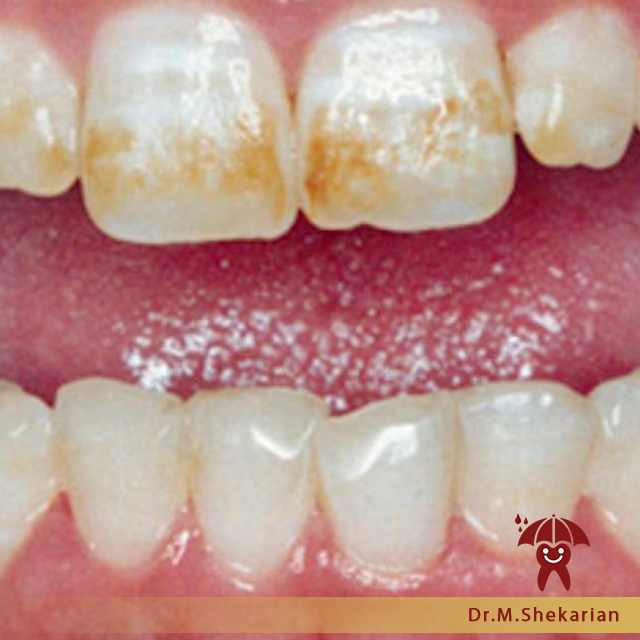

وارد شدن بیش از حد مجاز فلوراید توسط خوراکی ها و یا مکمل های غذایی به بدن کودک ، باعث بروز فلوروزیس دندانی در کودک میشود . اگر مقدار فلوراید مصرفی در کودک ، از حد مجاز (1ppm) بیشتر باشد و به صورت سیستمیک وارد بدن کودک شود، این لکه های سفید رنگ روی دندان دیده میشود. در موراد شدید تر شما شاهد لکه های زرد و قهوه ای بر روی دندان و حتی گاهی گود شدگی و تغییر شکل ظاهری مینا خواهید بود.

📌لکه های سفید گچی

📌در موارد شدید لکه های زرد و قهوه ای روی دندان

📌بد شکلی مینای دندان

📌فرورفتگی مینای دندان

یکی از سوالات رایجی که مادر پدران از ما میپرسند این است که این لکه های سفید چه خطراتی دارد؟ فلوروزیس های دندانی ، زیبایی دندان ها را تحت تاثیر قرار میدهد و خطر دیگری ندارد. حتی میتوان گفت که قسمتهایی از دندان که دچار فلوروزیس شده ، بسیار مقاومتر از مینای معمولی در مقابل پوسیدگی دندان میباشد . ولی برای بهبود وضعیت ظاهری دندان ، در آینده میتوان با کمک گرفتن از روش های ترمیمی – زیبایی این دندان ها را اصلاح کرد . موضوع اصلی که باید به آن پرداخت این است که میزان فلورایدی که وارد بدن کودک شده است چه مضرات و مسمویت هایی را بر ارگانهای کودک از جمله کبد و مغز کودک داشته است که این مساله با آزمایش مشخص خواهد شد.

نکته قابل توجه این است که فلوروزیس هیچ گاه باعث پوسیدگی دندان کودکان نخواهد شد و حتی دیده شده در قسمت هایی از دندان که فلوروزیس وجود دارد ، آن بخش از مینای دندان ، محکم تر از مینای بدون فلوروزیس است. ولی به طور کلی فلوروزیس دندانی از نظر زیبایی ظاهر خوشایندی ندارد.